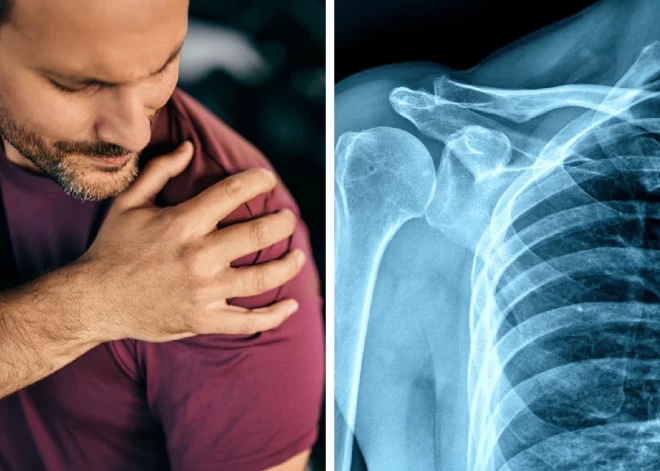

Sasaldēts plecs jeb adhezīvs kapsulīts ir locītavas kapsulas iekaisums. Locītavas kapsula ir blīva saistaudu plēve, kas no apkārtējiem audiem norobežo locītavas iekšējo telpu, kurā satiekas kaulu gali.

Normāli locītavas kapsula ir aptuveni trīs milimetrus bieza, bet pie iekaisuma var sabiezēt līdz pat centimetram un vairāk. Jo biezāka tā kļūst, jo mazāk elastīga kļūst. Un tas nozīmē, ka augšdelma kauls lēnām pieaug pie lāpstiņas, līdz ar to visas kustības, ko cilvēks veic ar pleca locītavu, viņš patiesībā veic ar lāpstiņu. Tātad, nepaceļot visu plecu, nav iespējams veikt kustību. Pilnībā zūd spējas rotēt roku uz āru. Visi audi – cīpslas, saites – saaug kopā.

Diagnozi noteikt ir diezgan grūti, un bieži vien pacienti staigā no viena ārsta pie cita, tā arī nesaņemot vajadzīgo palīdzību. Nereti cilvēks vispirms dodas pie sava ģimenes ārsta, kas nosūta pie neirologa. Kad pacients nonāk pie traumatologa, svarīgi saprast, ka cilvēkam ir sasaldētajam plecam raksturīgās pazīmes, kā arī veikt apskati. Pēc tam diagnozi vēlams apstiprināt ar ultrasonogrāfiju vai magnētisko rezonansi. Tikai pēdējos gados, attīstoties attēldiagnostikas iekārtām, to iespējams atklāt magnētiskās rezonanses izmeklējumā. Iepriekš attēli uzrādīja, ka ar plecu viss ir kārtībā, vai arī bija redzamas nebūtiskas izmaiņas.